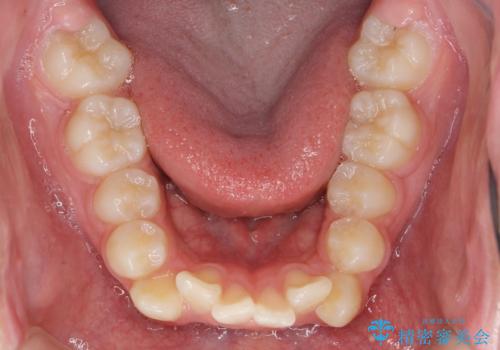

- 前歯のがたつきが原因で歯ブラシしづらい、見た目を改善したい!と矯正治療を希望され来院されました。

スペースの不足が見られるため、小臼歯の4本抜歯を行いマルチブラケットを用いた矯正治療を計画します。